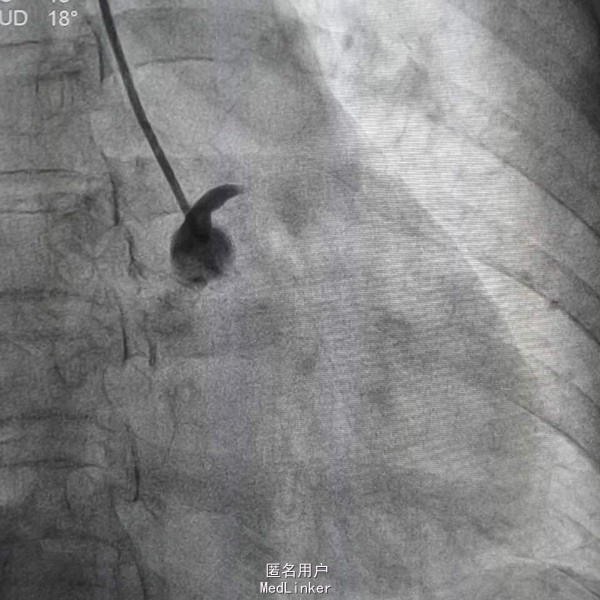

患者,女性,63岁,主因阵发性胸痛5天,加重15小时入院,既往否认高血压糖尿病史,无食物及药物过敏史,无不良嗜好。入院前一天剧烈胸痛晕厥一次,具体情况不详。

血压97/57mmHg,神清语明,口唇无发绀,颈静脉无怒张,双肺无啰音,心率82次每分,律齐,未闻及杂音,腹平软,肝脾未及,双下肢不肿。 辅查心电Il Ill avf ST段下移,avl V6 ST段抬高 白细胞14X109/L,D二聚体665ug/L,肌钙4.1ng/mL,

急性心肌梗死 心功能I级 处理,抗凝抗聚后行PCI治疗

造影示左主干闭塞,如图,预扩后快速送入支架行冠脉再通,此病人心电图很难判断左主干病变,值得警惕